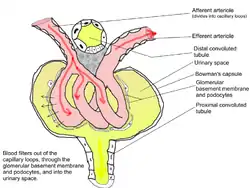

Glomerulus; note "Glomerular basement membrane and podocytes". | |

Renal corpuscle (glomerulus) showing glomular basement membrane.

Renal corpuscle (glomerulus) showing glomular basement membrane.